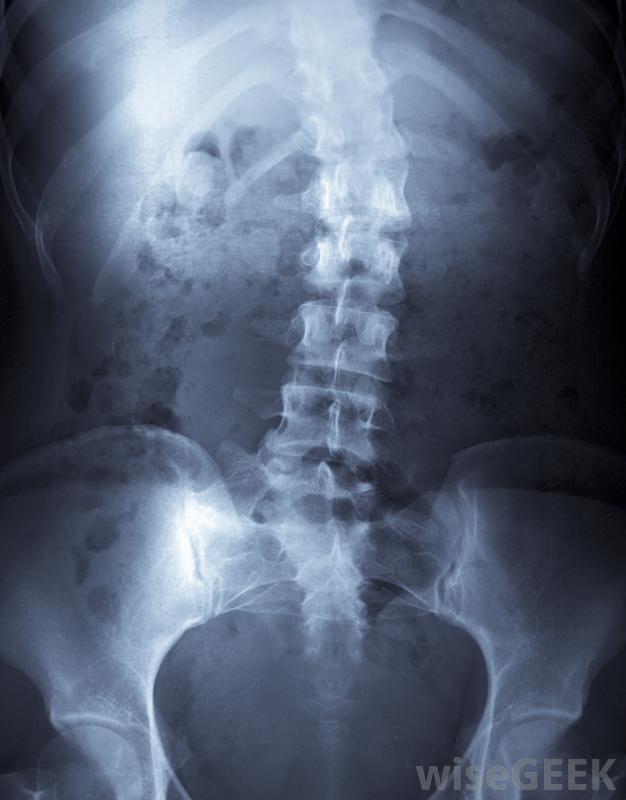

Cobb角用于测量脊柱侧凸患者的脊柱弯曲程度为了确定Cobb角,需要对脊柱进行X光透视,从后面观察患者。护理人员确定曲线的起点和终点,在曲线的起点和终点从椎骨上画出直线。对于一个脊柱笔直的人来说,这些线是平行的。对于脊柱弯曲的人,这些线沿着椎骨的斜面,并且是成角度的

对脊柱进行x光检查以确定Cobb角。